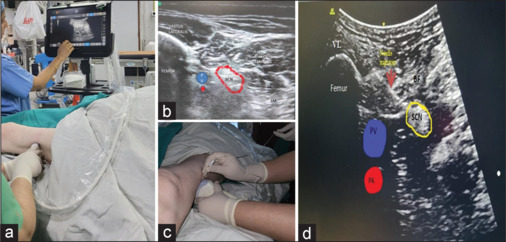

超声(US)引导下腘坐骨神经阻滞(PSNB)联合股神经阻滞(FNB)为膝下(BK)清创和截肢提供了足够的手术镇痛。本研究回顾性分析了16位美国麻醉医师协会身体状态III和IV的患者,描述了一种us引导的远端横向(横向)入路,在四肢处于中立位的情况下使用FNB进行仰卧侧位PSNB (CAPS)。可见度得分中位数为4分。阻滞表现的中位时间为8 min,达到感觉阻滞和运动阻滞的中位时间分别为20 min和25 min。CAPS阻滞与FNB是BK截肢和清创的可靠组合。

Ultrasound (US)-guided popliteal sciatic nerve block (PSNB) with a femoral nerve block (FNB) provides adequate surgical analgesia for below-knee (BK) debridements and amputations. This retrospective review of 16 American Society of Anesthesiologists physical status III and IV patients describes a US-guided distal transverse (crosswise) approach to perform supine lateral PSNB (CAPS) with FNB with the limb in the neutral position. The median visibility score was 4. The median block performance time was 8 min. The median time to achieve sensory and motor block was 20 and 25 min, respectively. CAPS block with FNB is a reliable combination for BK amputation and debridement.